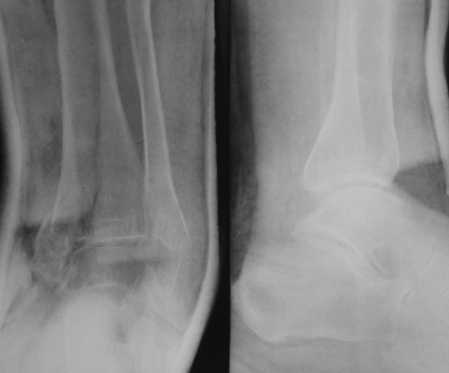

Посмотрели снимки после репозиции - не понравилась зона синдесмоза.

Сделали 3/4-е - впечатление, что в 99-том там что-то было. На

5.11.09г. запланирована КТ.

На сегодня остаются, хотя и в более осторожной формулировке, вопросы

по дальнейшему лечению:

1. С учетом анамнеза и развалившегося метаэпифиза, можно-ли

надеяться на консолидацию если оставить все "как есть"?

2. Если "нет", то каков рациональный объем хирургической агрессии?